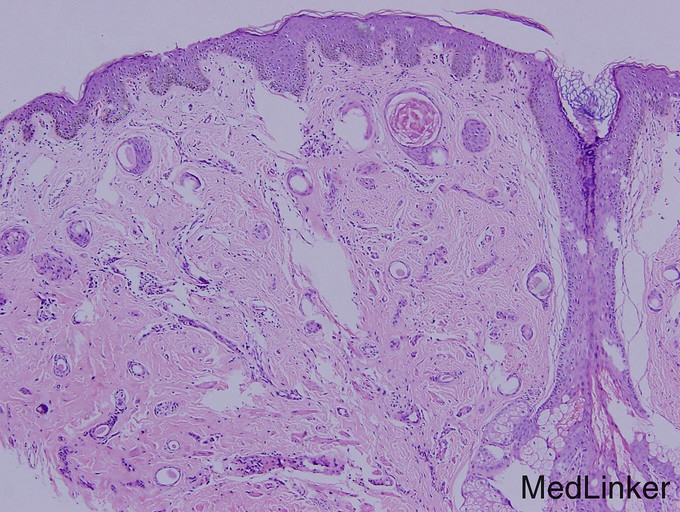

体检:体温36.5℃,脉搏72次/分,呼吸16次/分,血压124/60mmHg。发育正常,营养良好,面容正常,自主体位,步态蹒跚,神清,查体合作。实验室检查:左下腹可见一纵形陈旧性手术疤痕,腹柔软,无压痛反跳痛,未触及包块。心肺听诊无异常。专科体征:躯干以背部为主较多黑褐色丘疹,略粗糙,面部少许类似皮损。 辅助检查:血尿粪常规、肝肾功能均正常。2000年结肠增生物切除物病理学检查:腺样结构,腔侧细胞呈高柱状,胞浆淡染,周边细胞胞浆呈嗜碱性,其中可见核大浓染细胞和病理性核分裂。

Leser-Trelat症首先由Edmund Leser和Ulysse Lrelat描述,1900年Hollander首次强调Leser-Trelat症与内脏肿瘤的关系。本症可单独发生,亦可同时与肿瘤并存,故学者们将此种皮肤损害称为内脏肿瘤的标志,故长期以来,本病一直被认为是一种皮肤副肿瘤性综合征。临床上,Leser-Trelat症是指突然出现多发性脂溢性角化或原有的脂溢性角化损害突然增大、数目增多,就每个损害而言,Leser-Trelat症的脂溢性角化与一般的脂溢性角化相同,分布也相似,多数损害位于背部和胸部,其次为四肢、面、腹和腋部,但也可泛发,通常上肢多下肢,可伴有不同程度的瘙痒。 Leser-Trelat症多伴发腺癌,主要发生在食管和胃,也有合并白血症或蕈样肉芽肿的报道。本例患者依据典型的脂溢性角病皮损、结肠组织病理学变化可确诊。